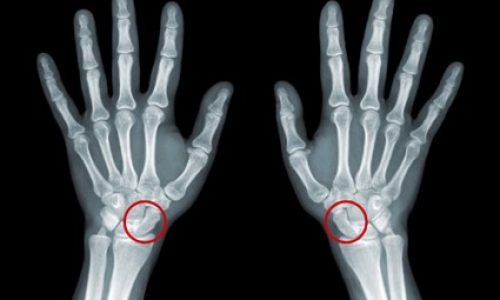

Os sinais de pseudoartrose geralmente aparecem quando o paciente percebe que o tempo de recuperação está sendo mais longo do que o esperado. A dor persistente é um dos principais sintomas, especialmente quando continua presente meses após a fratura. Outro sinal característico é a sensação de instabilidade ou movimento anormal no local, dificultando atividades simples como caminhar ou apoiar peso. Para confirmar o diagnóstico, o médico realiza exame clínico e solicita exames de imagem. O raio-X é o mais utilizado, pois revela a ausência de calo ósseo. Em alguns casos, a tomografia e a ressonância magnética são necessárias para avaliar detalhes como irrigação sanguínea, necrose óssea ou presença de infecção.